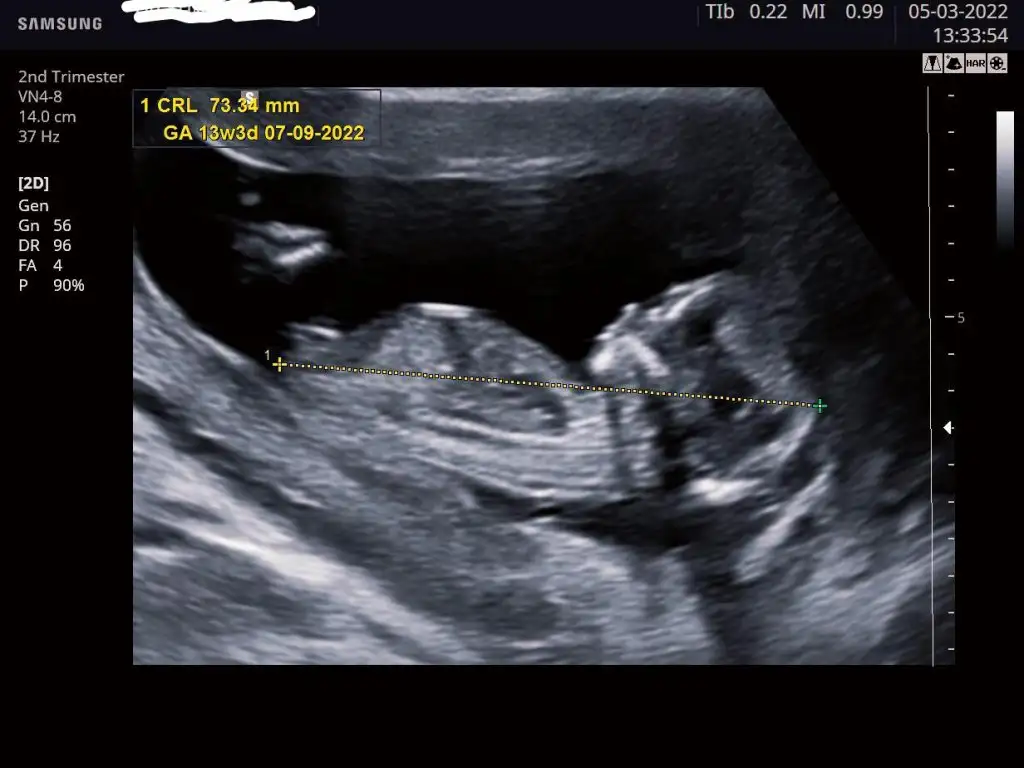

Ayyyyy büyümüş ya bu... Yesin teyzesi onunyaaa MashaAllah kuzuma..11+2 de olan görüntümüz karından bakıldı bana da bi tahminde bulunur musunuz![]()